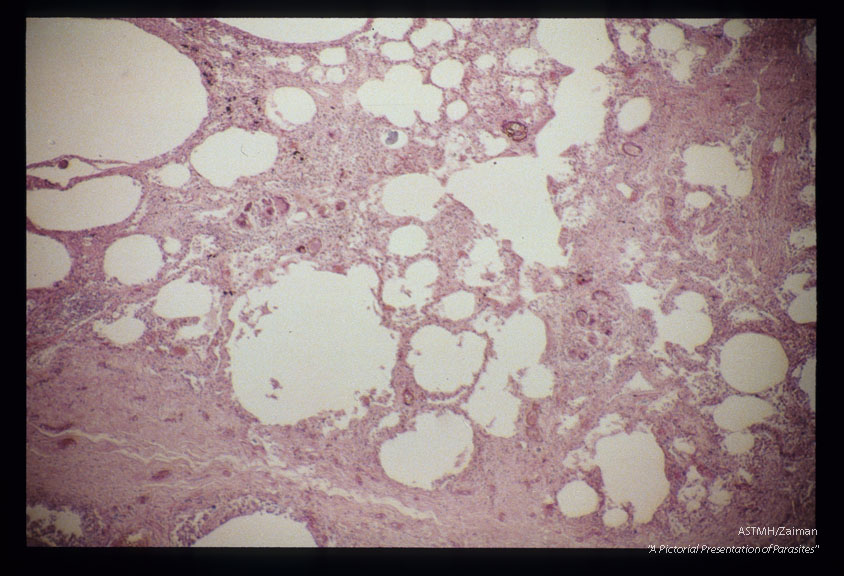

Section of lung from 16 year old Philippine female who died of schistosomal pneumonitis.

Schistosoma japonicum

Description: Section of lung from 16 year old Philippine female who died of schistosomal pneumonitis.